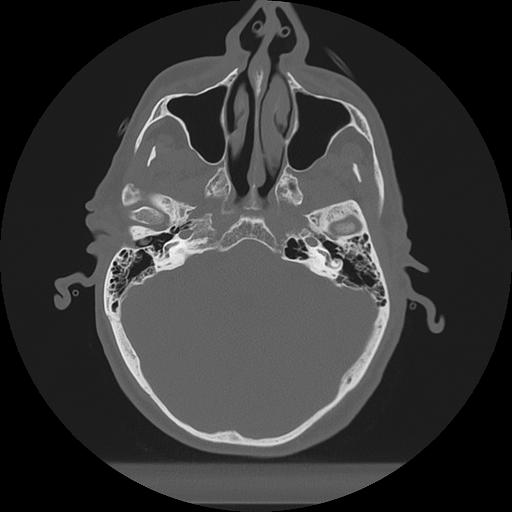

11 HUESO,,Axial,2.0,HUESO,,